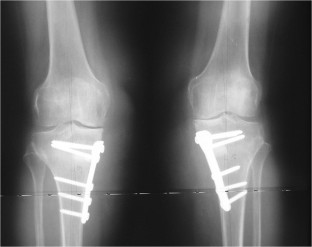

Fig. 1